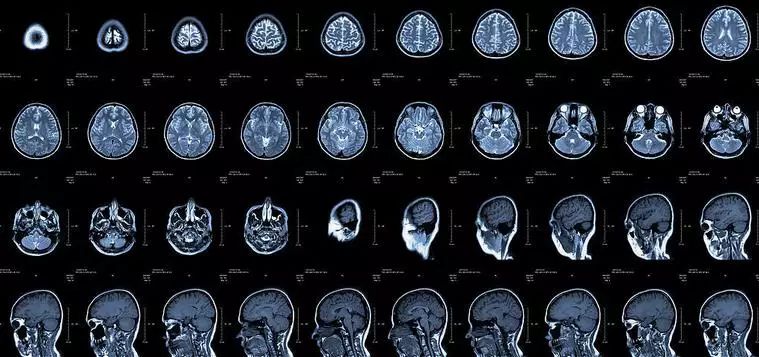

核磁共振(MRI):进入磁场,让体内氢原子核摇一摇,感受震动,评估检查结果

原理:利用收集磁共振现象所产生的信号而重建图像的成像技术,简单说就是相当于用手机摇一摇,让氢质子振动起来,再平静下来,感受一下里面的振动。

优点:与CT相比,它没有放射辐射,没有骨性伪影,能多方面、多参数成像,有高度的软组织分辨能力。

缺点:费用相对比较昂贵。

磁共振的远离简单的说:正常情况下人体内的氢原子核处于无规律的进动状态,当人体进入强大均匀的磁体空间内,在外加静磁场功能下原来杂乱无章的氢原子核一齐按外磁场方向排列并继续进动,当立即停止外加磁场磁力后,人体内的氢原子将在相同组织相同时间下回到原状态;这称为驰豫,而病理状态下的人体组织驰豫时间不同,通过计算机系统采集这些信号经数字重建技术转换成图像就能够给临床和研究提供科学的诊断结果。

磁共振和CT的区别主要在于成像的性质,CT是根据组织的密度,由于人体不同组织的密度不同,来发现病灶;而磁共振是判断不同加权所产生的不同信号。磁共振于对软组织滑膜、血管、神经、肌肉、肌腱、韧带、和透明软骨的分辨率高。由于其特殊的性质,磁共振看骨头不行,而在大脑的检查中则有着不可替代的功能。